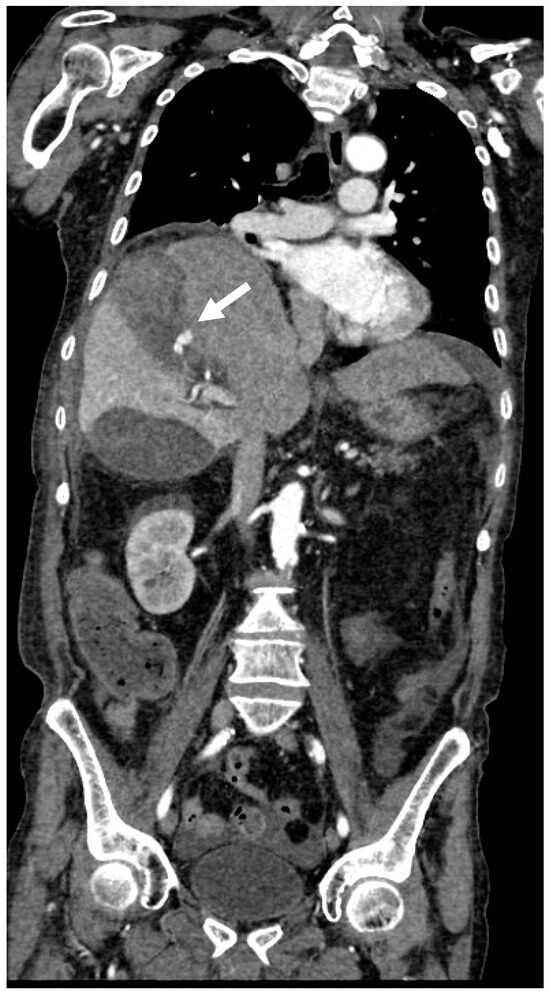

2. Imaging

3.1.3. Imaging and Diagnostic Findings